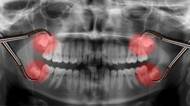

Pokud začnou zlobit takzvané zuby moudrosti, je o trápení postaráno. Způsobit komplikace mohou i ve chvíli, kdy se prořezávají, což bývá hodně dlouho po všech ostatních zubech. Proč se osmičky neprořezávají v dětství a je nutné je vždy vytrhnout? Kdy a jak dlouho rostou zuby moudrosti, proč to někdy tak bolí a k čemu je vlastně máme, když stejně většinou nakonec dojde k jejich odstranění, často z preventivních důvodů?